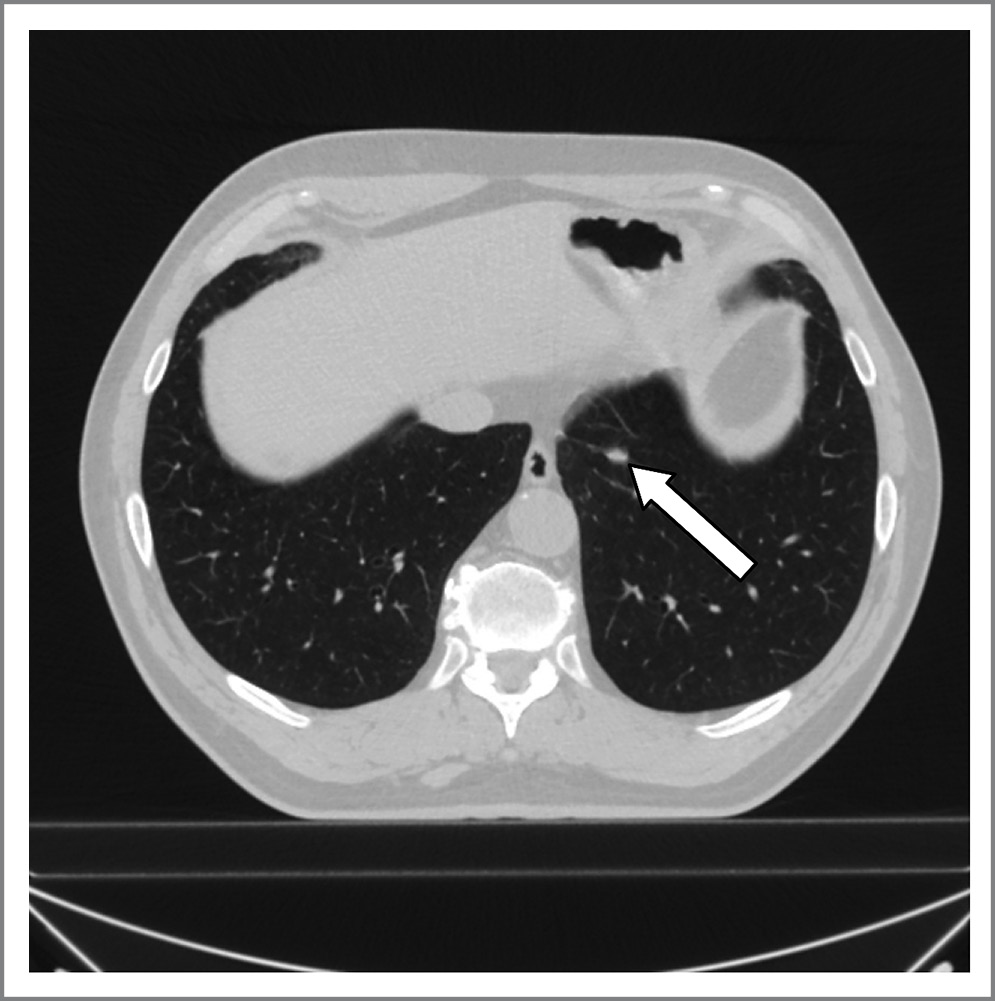

У жителя г. Воронежа 68 лет в 2016 г. диагностирован рак левой почки и выполнена левосторонняя нефрэктомия. Пациент получил 3 курса химиотерапии и ежегодно проходил углубленное обследование. В феврале 2019 г. проведено контрольное обследование – компьютерная томография (КТ) органов грудной клетки. По данным КТ в нижней доле левого легкого SIX «обнаружен очаг, предлежащий к уплотненной междолевой плевре, размером 0,9×0,5 см» (рис. 1).

Рис. 1. КТ органов грудной полости с очагом в нижней доле левого легкого.

Fig. 1. Computed tomography of the chest with a lesion in the lower lobe of the left lung.

При повторно выполненной КТ 24.10.2019 отмечено «увеличение размеров новообразования до 1,5×1 см, остальные уплотнения на междолевой плевре без динамики». Других очагов во внутренних органах и центральной нервной системе не обнаружено. Выявленные изменения послужили основанием для направления пациента на хирургическое лечение, а сам очаг расценен как метастаз.